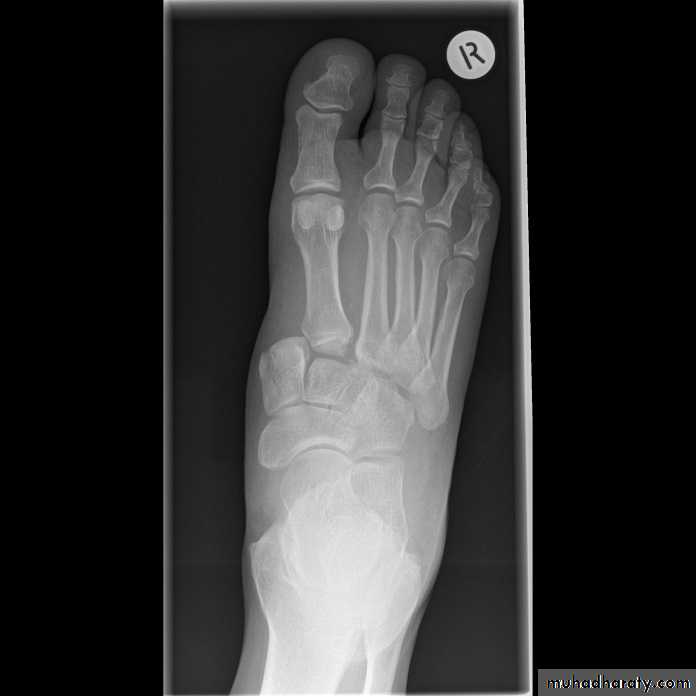

A condition characterized by disruption between the articulation of the medial cuneiform and base of the second metatarsal

unifying factor is disruption of the TMT joint complex

injuries can range from mild sprains to severe dislocations

may take form of purely ligamentous injuries or fracture-dislocations

ligamentous vs. bony injury pattern has treatment implications

Lisfranc Injury (Tarsometatarsal fracture-dislocation